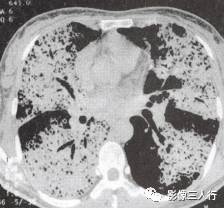

胸部CT图像显示,在含气少的致密肺的背景上见到含气的支气管,表现为两种形态: ①在大片肺实变病灶内的细条状空气密度影;②直径Imm的小泡状空气密度影,连续的几 个层面都能出现(图2、图3)。该征象表明:①近侧气道通畅;②肺泡内的空气经吸收(肺不张)或取代(肺炎、肺癌),或两者综合而消失。通畅含气的支气管在肺泡实变高 密度区内表现为管腔内低密度充气轮廓。